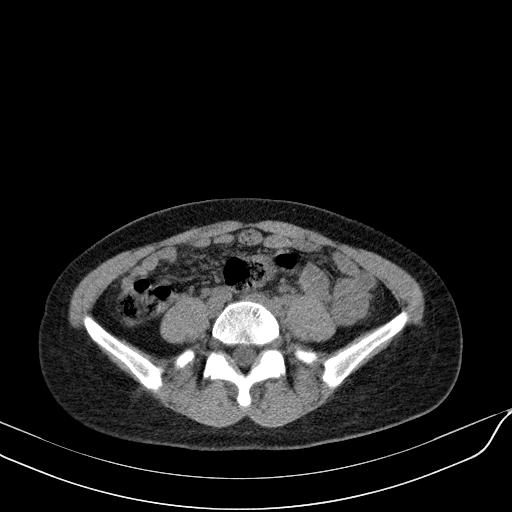

标题: CT23965:无外伤史,下腹痛 [打印本页]

标题: CT23965:无外伤史,下腹痛

无外伤史,下腹部疼痛!---------正常

肠道未准备,继续往下扫,乙状结肠占位不排除。建议钡灌或结肠镜检查。

乙状结肠占位不排除

未见明显异常改变,做个气钡双重造影除外一下结肠病变,无外伤史为啥不常规喝泛影葡胺水对比剂再扫ct呢?

肠道肿瘤,建议行钡剂灌肠检查。